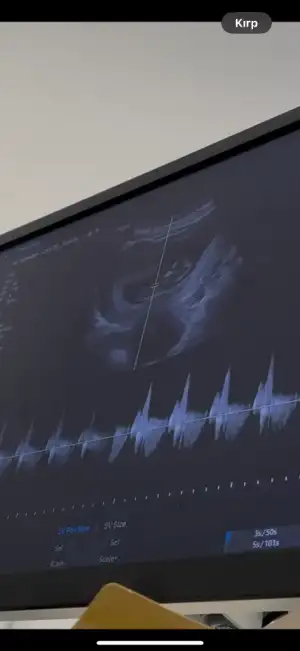

Cinsiyet tahmin

Senın kızın olcakEki Görüntüle 3582103 kızlar sizce cinsiyeti ne 12+6 haftalık burda

Nubu eğik duruyor kız gibi maşallah Allahım esirgesinEki Görüntüle 3582103 kızlar sizce cinsiyeti ne 12+6 haftalık burda

Bizede bakabilir misiniz görsellerde ilki 10+4 diğer görseller 6+4 ten çok heyecanlıyızzNubu eğik duruyor kız gibi maşallah Allahım esirgesin

Ay canım benim Allahım gönlüne göre versin ama nubu belli olmuyor ne desem yalan olur ha yine de içimden kız geçti sağlıkla gelsinBizede bakabilir misiniz görsellerde ilki 10+4 diğer görseller 6+4 ten çok heyecanlıyızz))